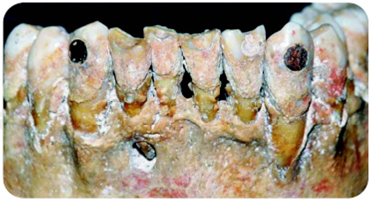

En términos generales afirma Fastlicht que los tejidos periodontales pocas veces fueron lesionados por técnica defectuosa en la manipulación del diente, para la preparación de la cavidad destinada a la incrustación.24 Sin embargo, existen ejemplares en los que se observan las huellas de lesión alveolar causada probablemente por el aumento de temperatura generado por la fricción del desgaste, dando lugar a grandes abscesos formados en torno al vértice de la raíz de los incisivos y caninos superiores, o bien la pérdida de dientes aislados y cuyos dientes contiguos con incrustaciones hacen suponer que la pieza faltante igualmente estuvo incrustada, pero de manera defectuosa, lo cual desencadenó una proceso infeccioso que acabó por provocar su pérdida ( Figura 10 ).25

Figura 10 Fragmento de cráneo prehispánico con incrustación de jade, cavidades vacías en dientes contiguos y una amplia lesión en periápice de incisivo lateral derecho.